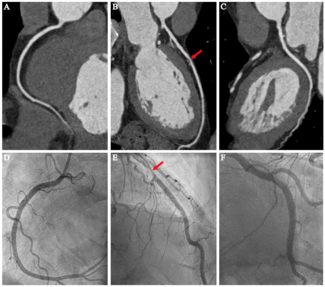

Julia L. Custodio, MD; Luiz C. Bergoli, MD, MSc; Gustavo Neves de Araujo, MD, PhD

A 93-year-old female patient with previous history of hypertension, atrial fibrillation, and ischemic stroke presented at the emergency department due to epigastric pain, malaise, sweating, and somnolence with 24 hours of evolution. Clinical...